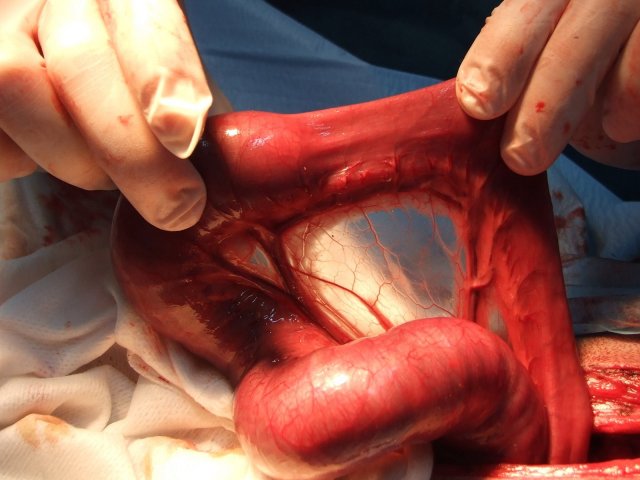

Lineární cizí těleso u 11měsíčního ridgebacka - z rozkousané bundy se zipem a plastového předmětu se vytvořilo lineární cizí těleso bezprostředně ohrožující život, které se na jednom konci zachytilo v žaludku a na druhý konec se navlékla cca 1/2 tenkého střeva. Za ní se bohužel vytvořila tzv invaginace - vchlípení jednoho úseku tenkého střeva do druhého. Kovový jezdec, který byl velmi dobře patrný na rentgenu, byl paradoxně volně v tlustém střevě a nezpůsoboval významnější obtíže. Museli jsme na několika místech vstoupit do žaludku a střev, přerušit a vyjmout cizí těleso, uvolnit vchlípení, zrevidovat životaschopnost střev a po zhodnocení stavu a perfuze krví uvést vše do původního stavu a dutinu břišní po výplachu uzavřít. Pacientovi se daří dobře, střeva fungují a už sám přijímá potravu.